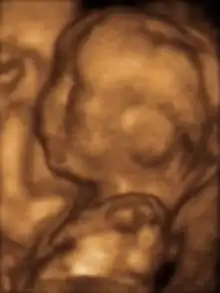

صور تخطيط الصدى ثلاثية الأبعاد المتقدمة توفر تفاصيل أكبر لتشخيص ما قبل الولادة، أكثر من تقنيات تخطيط الصدى ثنائية الأبعاد القديمة.[6] على الرغم من أن ثلاثي الأبعاد له شعبية كبيرة لدى الآباء الذين يرغبون بالحصول على صورة كتذكار[7] إلا أن إدارة الغذاء والدواء لا توصي باستخدام أي من ثنائي الأبعاد أو ثلاثي الأبعاد في غير الاستخدامات الطبية،[8] ولكن لا توجد دراسات حاسمة تربط تخطيط الصدى بأية أعراض جانبية طبية.[9] صور تخطيط الصدى ثلاثية الأبعاد التالية التقطت في مراحل مختلفة من الحمل:

جنين عند 20 أسبوعا.